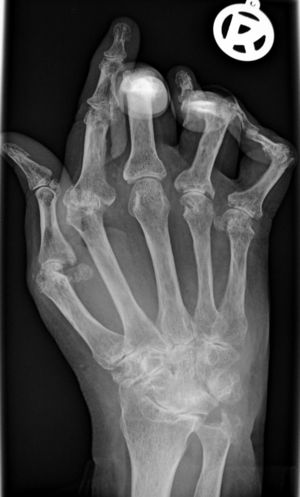

التهاب المفاصل الرثياني أو الروماتويد Rheumatoid arthritis (RA) ، هو أحد الالتهابات المزمنة التي تنشأ من خلل في الجهاز المناعي للجسم، وتصيب الأغشية المبطنة للمفاصل ، خاصة المفاصل الصغيرة مثل مفاصل اليدين و الرسغين ، وفي الحالات المتأخرة قد يزيد الوضع ويتفاقم ليحدث تلفاً تدريجياً للمفاصل واعوجاجاً وتشوهاً في بعضها.

ويتميز مرض الروماتويد بأنه يبدأ تدريجياً بتيبس والتهاب مفاصل اليدين والساقين في الصباح الباكر، ثم يلاحظ انحراف في مسار اليد عكس الجسم مع خلع في مفاصل اليد، ووجود بثور على سطح الجلد للساقين بنسبة 20%، مع الآم متواصلة، خاصة أثناء النوم وفقدان حركة المفصل، وأخيراً إصابة المفاصل في أنحاء متفرقة من الجسم بتشوهات مثل مفاصل اليدين والركبتين والكاحلين والرقبة والحوض.

ويتم التأكد من التشخيص بعمل فحص للدم والذي يشير هنا إلى ارتفاع في نسبة ترسب الدم ESR ووجود عامل الروماتويد RF وكذلك وجود سي ـ ر ـ بروتين CRP وكذلك عمل أشعة سينية وهي توضح هنا تغيرات في المفاصل مثل تآكل المفاصل وتشوهها وهشاشة العظام.